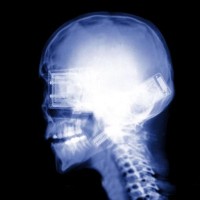

Pada tulisan ini kami ingin melaporkan tentang kasus dimana pen yang terpasang terlalu lama dan tidak dilepas dapat menyebabkan masalah. Pemasangan pen pada kasus patah tulang umum dilakukan oleh dokter bedah tulang. Banyak orang yang belum tahu apa sih “PEN”.

Sebenarnya istilah “PEN” kami dapat dari obrolan 2 dimasyarakat yang dimaksud adalah implant yang dipasang pada tulang dengan maksud untuk mempertahankan kedudukan tulang dalam posisi yang benar (anatomis) sampai proses penulangan terjadi .

Tujuan pemasangan pen agar penderita lebih cepat melakukan aktifitas sehabis operasi dengan bantuan atau tanpa bantuan alat bantu. Banyak jenis pen yang dipakai di bidang Orthopedi, tergantung dari jenis tulang dan jenis patahan tulangnya, oleh sebab itu pada kasus yang berbeda sudah pasti jenis pen yang dipasang berbeda.

Di pasaran yang ada saat ini pen terbuat dari stainless steel atau titanium, sudah terbukti bahwa titanium lebih bagus dari stainless steel , karena reaksi penolakan tubuh hampir tidak ada dibanding stainless , lebih ringan dan lebih kuat, daya adhesi terhadap kuman lebih rendah dibanding stainless,sehingga memang Titanium lebih baik dari pada stainless, cuma saja harganya cukup mahal, dan stock di pasaran sedikit sehingga harus di pesan dulu, sehingga untuk kasus emergensi agak sulit kita lakukan.

Pada pen yang seperti contoh pada gambar umumnya terbuat dari stainless, dimana sifat reaksi penolakan tubuh lebih banding titanium dan daya adhesi kuman pada permukaan lebih tinggi,sehingga di anjurkan bila tulang sudah menyambung pen di lepas saja.

Keuntungan pelepasan pen adalah : membuat daya elastis tulang yang terpasang pen kembali seperti semula, tulang lbh kuat,mencegah terjadinya reaksi penolakan tubuh terhadap pen. Pada gambar ini kami laporkan contoh kasus rekasi penolakan setelah dipasang pen 17 tahun , dimana terjadi infeksi pada kulit di daerah sekitar pen yang dipasang.(pada kasus patah tulang kering)

Jadi kesimpulan sebaiknya pen dilepas setelah tulang menyambung (rata2 1 tahun), apalagi pada anak2 harus dilepas segera karena dapat mengganggu pertumbuhan tulang, khusus pada orang lanjut usia bila tidak ada keluhan tidak perlu, tapi lebih baik di lepas bila ada keluhan.